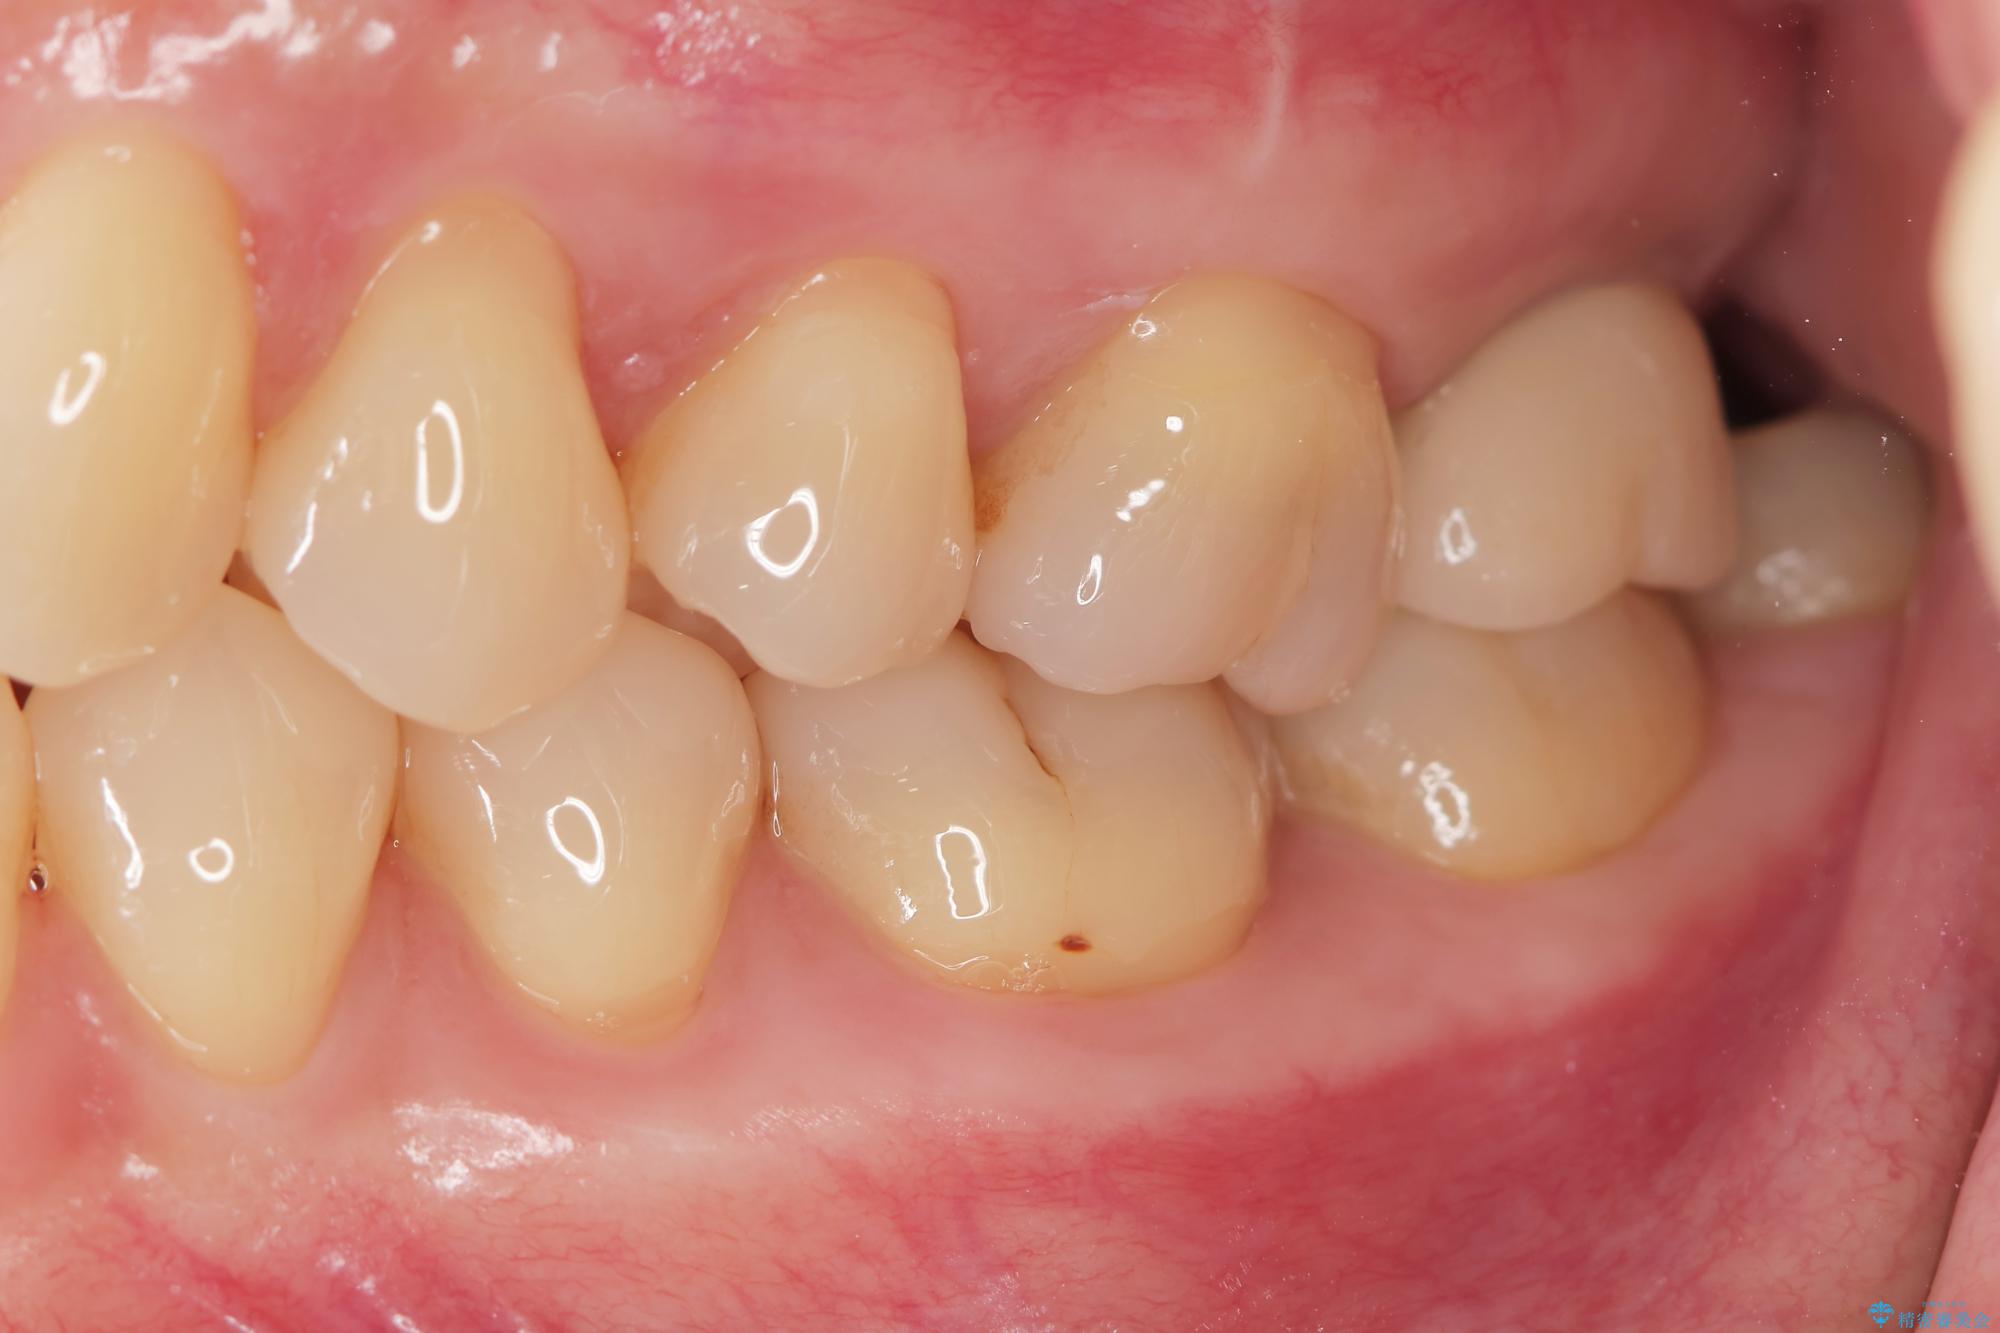

精査した結果、上顎奥歯は歯が割れてしまっており、根管治療ではなく抜歯の対象でした。

治療前

【噛むと歯が疼く】歯牙破折からのインプラント治療 治療前画像 【噛むと歯が疼く】歯牙破折からのインプラント治療 治療前画像 【噛むと歯が疼く】歯牙破折からのインプラント治療 治療前画像 【噛むと歯が疼く】歯牙破折からのインプラント治療 治療前画像 【噛むと歯が疼く】歯牙破折からのインプラント治療 治療前画像 【噛むと歯が疼く】歯牙破折からのインプラント治療 治療前画像 【噛むと歯が疼く】歯牙破折からのインプラント治療 治療前画像